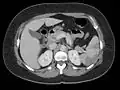

Blood clots in the ventricle found on autopsy

Echocardiography is the main diagnostic tool for LVT. A distinct mass is visible in the left ventricle. Computed Tomography and Magnetic Resonance Imaging are effective, but less common ways to detect LVT, due to their costs and risks.[1] It is possible to assess whether a thrombus will become an embolus through echocardiography. Mobility and protrusion of the thrombus are two characteristics associated with increased embolic potential.[8]